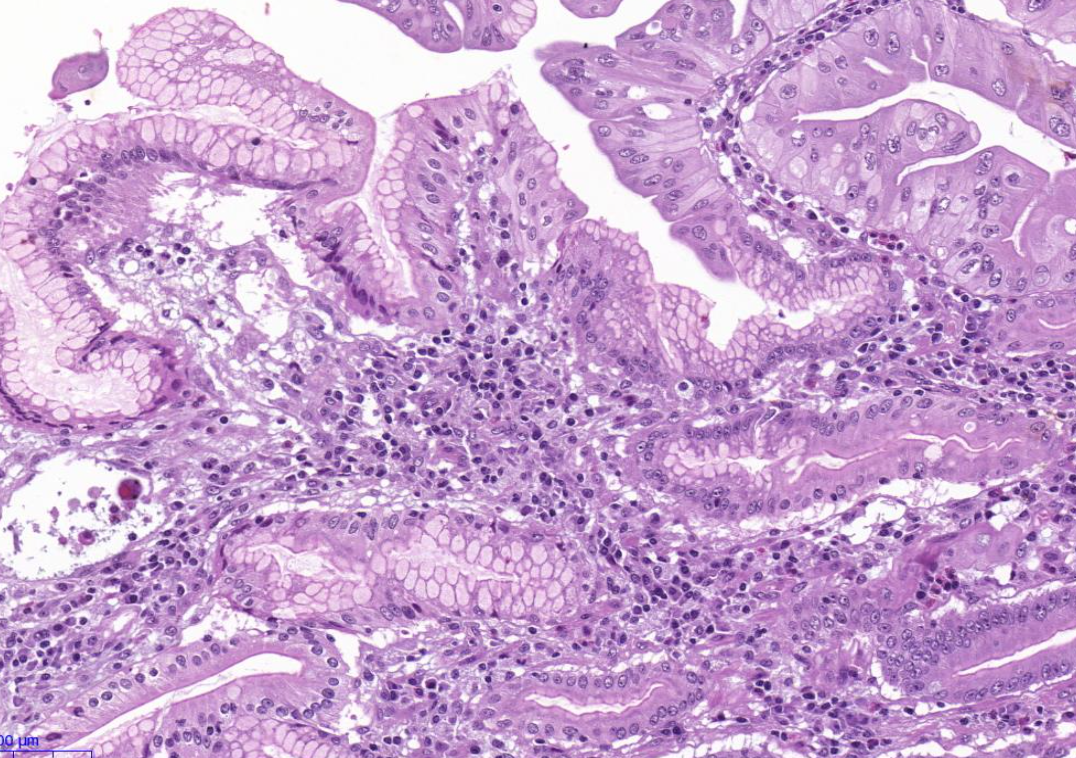

Diagnose?

Barettmetaplasie (dunkelviolett = mit Dysplasie)

Durch Reflux -> Metaplasie (nicht maligne) der Epithelien, intestinalisiertes Epithel/ Becherzellen, Biopsate mit Plattenepithel und Zylinderepithel (nur dann weiß man es ist Übergangsbereich)

Barrett-Zelle = Becherzelle

Barettmetaplasie mit Dysplasie

-> Erkennt man an Becherzellen